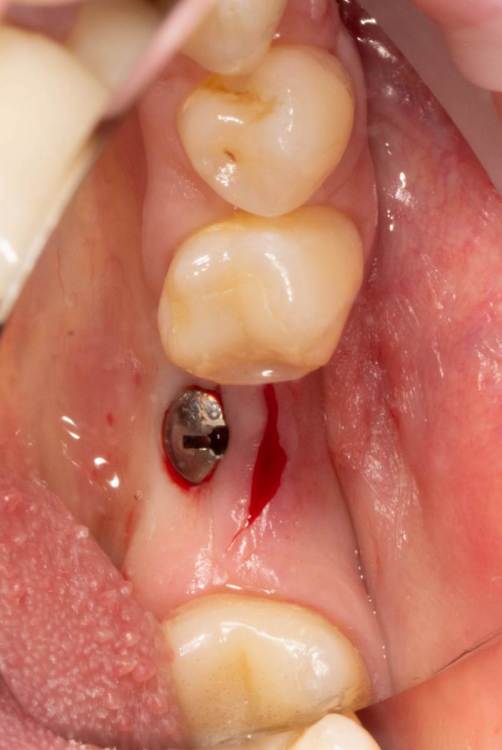

Женька Опубликовано 19 июня, 2023 Поделиться Опубликовано 19 июня, 2023 Здравствуйте, коллеги. Примерно с нового года начал ставить ТЛ имплантаты Дентиум. Что-то под заглушку (не поймал торки, представляете?). Что-то на низких формирвателях. И вот пришла пора протезирования, но отпустить к ортопеду не подготовив десну - не получается. Создал сам себе проблем, сегодня вот исправлял. Получилось неплохо? 3 Ссылка на комментарий

TIGER Опубликовано 20 июня, 2023 Поделиться Опубликовано 20 июня, 2023 Это ж не TL,cубкрестально же.А так я бы длиннее брал ССТ,с захватом соседей Ссылка на комментарий

Женька Опубликовано 20 июня, 2023 Автор Поделиться Опубликовано 20 июня, 2023 @TIGER в смысле это не ТЛ?))) Фото с редукцией не сделал. А то что, шейку погружал - так нужно было. Но это ТЛ. Поверьте) я был на имплантации) Ссылка на комментарий

АнтонТЛТ Опубликовано 20 июня, 2023 Поделиться Опубликовано 20 июня, 2023 Думаю имеется ввиду что имплантат TL установлен по протоколу BL Ссылка на комментарий

Женька Опубликовано 20 июня, 2023 Автор Поделиться Опубликовано 20 июня, 2023 @АнтонТЛТ мы же позиционируем платформу относительно зенита? Есть ли разница тогда, какой имплантат мы выбираем? Вообще весь смысл здесь был заложен в том, что толщина гребня была не очень. Хотелось поставить тонкий имплантат 3.6. Но рисковать тонкой платформой не хотелось, поэтому выбор пал на 4.8 платформу ТЛ и тело имплантата 3.6 1 Ссылка на комментарий

АнтонТЛТ Опубликовано 20 июня, 2023 Поделиться Опубликовано 20 июня, 2023 Конечно относительно зенита, не вдаваясь в подробности, для BL глубже зенита на 3мм, для TL вровень с зенитом. Ссылка на комментарий